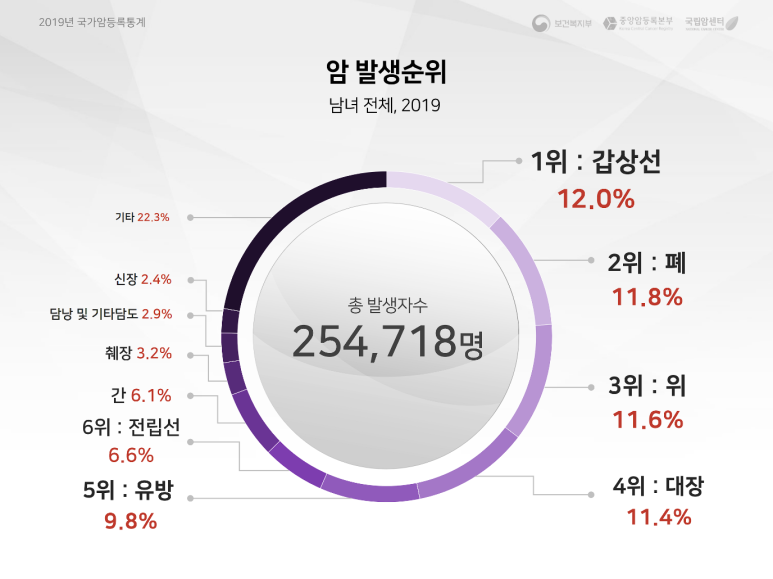

용인항유외과 유방갑상선센터 진료실과 초음파실 갑상선암 검진을 왜 해야 하나요?먼저 통계를 보면 갑상선암은 우리나라에서 가장 발생률이 높은 암으로 발표됐습니다.(2019년 국가암등록통계-2021/12/29 중앙암등록부 발표)

국가암등록통계자료

전체 암 발생자 수를 보면 1위 갑상선암, 2위 폐암, 3위 위암 순으로 발병할 것으로 보입니다.

다른 암종과 비교하면 갑상선암은 15~64세의 젊은 분들에게 주로 발생하는 것도 볼 수 있습니다.